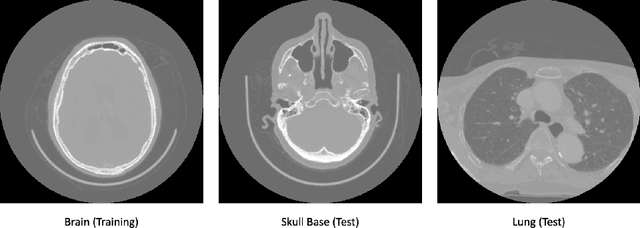

Abstract:Despite the great potential of machine learning, the lack of generalizability has hindered the widespread adoption of these technologies in routine clinical practice. We investigate three methodological pitfalls: (1) violation of independence assumption, (2) model evaluation with an inappropriate performance indicator, and (3) batch effect and how these pitfalls could affect the generalizability of machine learning models. We implement random forest and deep convolutional neural network models using several medical imaging datasets, including head and neck CT, lung CT, chest X-Ray, and histopathological images, to quantify and illustrate the effect of these pitfalls. We develop these models with and without the pitfall and compare the performance of the resulting models in terms of accuracy, precision, recall, and F1 score. Our results showed that violation of the independence assumption could substantially affect model generalizability. More specifically, (I) applying oversampling before splitting data into train, validation and test sets; (II) performing data augmentation before splitting data; (III) distributing data points for a subject across training, validation, and test sets; and (IV) applying feature selection before splitting data led to superficial boosts in model performance. We also observed that inappropriate performance indicators could lead to erroneous conclusions. Also, batch effect could lead to developing models that lack generalizability. The aforementioned methodological pitfalls lead to machine learning models with over-optimistic performance. These errors, if made, cannot be captured using internal model evaluation, and the inaccurate predictions made by the model may lead to wrong conclusions and interpretations. Therefore, avoiding these pitfalls is a necessary condition for developing generalizable models.